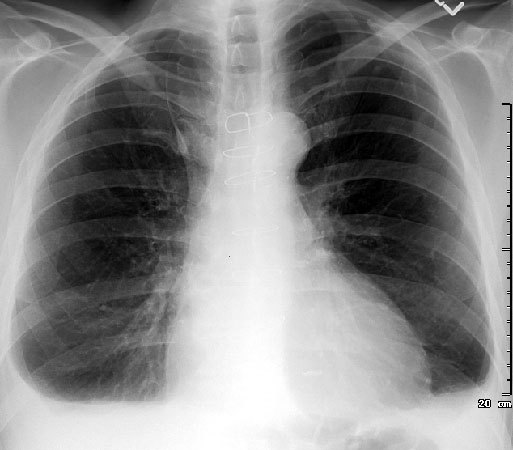

What is the main abnormality on this CXR and how do you know?

Describe the abnormality/ies

Hilar shadowing

(Hilar lymphadenopaty)